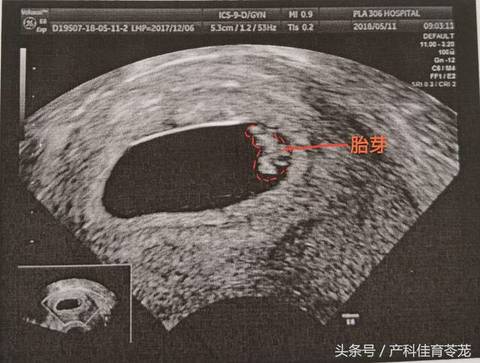

阴超胎芽

上周去只看到卵黄囊,今天去担心腹部看不清就选择了阴超,医生说有胎芽